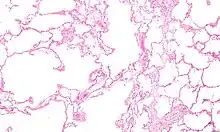

Micrograph showing emphysema (left – large empty spaces) and lung tissue with relative preserved alveoli (right)

Narrowing of the airways occurs due to inflammation and subsequent scarring within them. This contributes to the inability to breathe out fully. The greatest reduction in air flow occurs when breathing out, as the pressure in the chest is compressing the airways at this time.[97] This can result in more air from the previous breath remaining within the lungs when the next breath is started, resulting in an increase in the total volume of air in the lungs at any given time, a process called air trapping which is closely followed by hyperinflation.[97][98][92] Hyperinflation from exercise is linked to shortness of breath in COPD, as breathing in is less comfortable when the lungs are already partly filled.[99] Hyperinflation may also worsen during an exacerbation.[100] There may also be a degree of airway hyperresponsiveness to irritants similar to those found in asthma.[87]